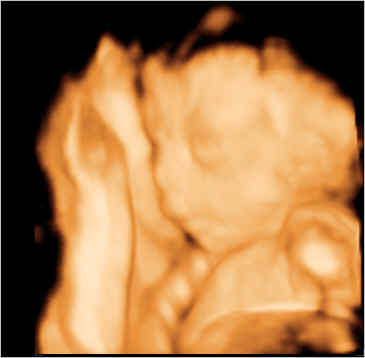

3-D УЗИ, пол малыша

Результаты: УЗИ, КТГ, доплера, скринингаВчера, на 24-й неделе, сходили на 3-D УЗИ. Восторгов не передать словами!!! Ребеночек очень симпатичный, славное личико и не такой худенький, как я думала.

Все параметры в норме, ручки-ножки на месте, внутренние органы тоже.